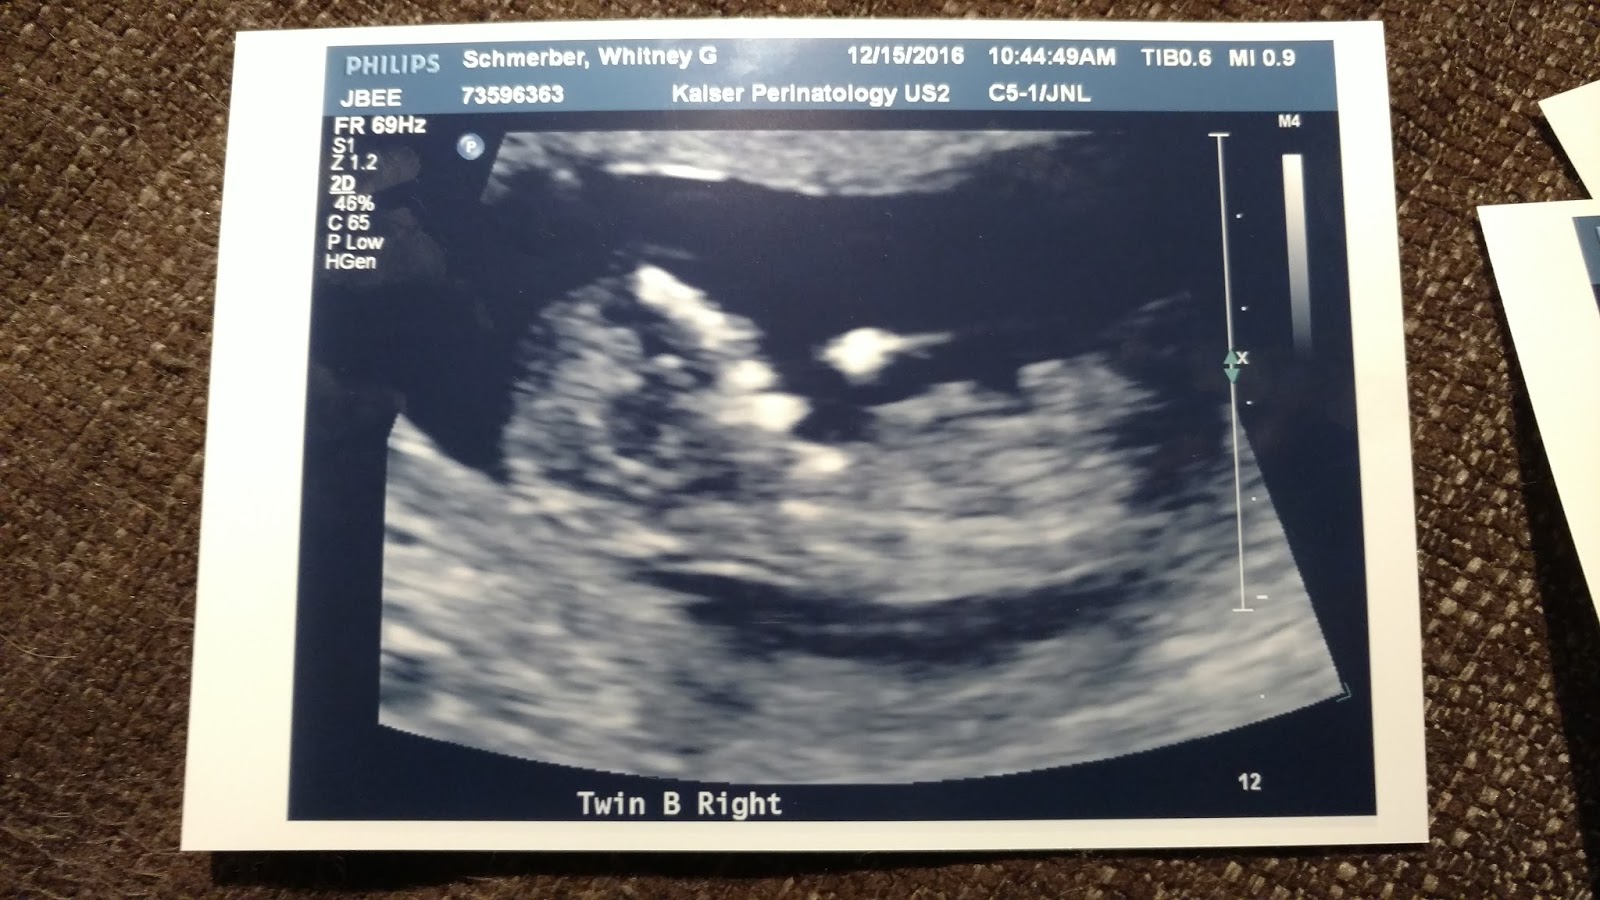

Here are a couple pictures from the ultrasound:

Twin B waving to the camera